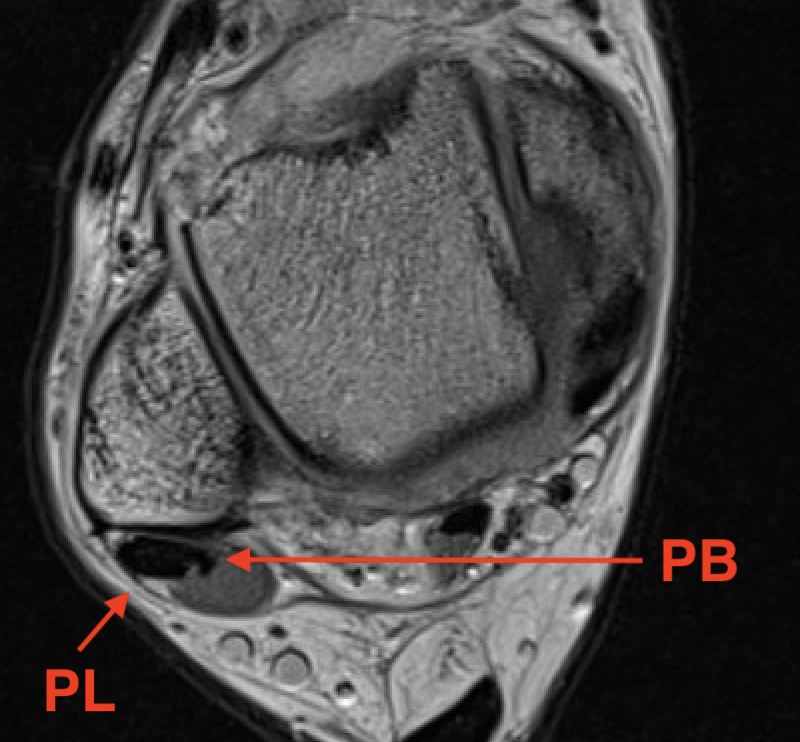

Anatomy

| Peroneus longus | Peroneus brevis | |

|---|---|---|

| Origin |

Lateral condyle of tibia and head fibula Tendon superficial to PB in retromalleolar groove |

Middle third fibula and intermuscular septum |

| Insertion |

Plantar surface base of 1st metatarsal Lateral aspect medial cuneiform |

Tuberosity base 5th metatarsal |